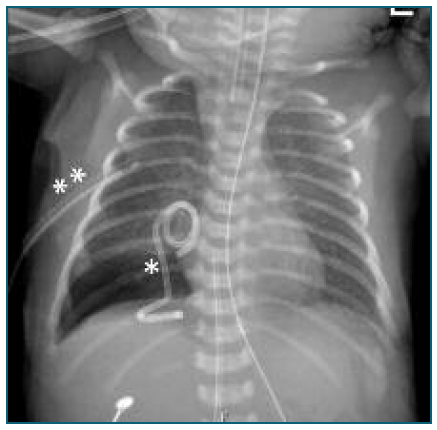

There was worsening of respiratory difficulty under non-invasive ventilation in the first hours of life, and a chest X-ray (Figure 7) revealed a large right pleural effusion. In this context, invasive ventilation and thoracentesis (pleural fluid with characteristics of chylothorax, negative bacteriological examination) were performed, followed by placement of a chest tube. Approximately 40 mL/day was drained with progressive reduction. Accidental removal of the chest tube occurred on day 4, with radiological surveillance showing complete resolution of the effusion by day 13. Room air was achieved by day 5 of life. The newborn was discharged from the hospital at 38 days of life, exclusively breastfed, with no recurrence of pleural effusion. Reevaluation at 2 months in clinic (corrected age of 2 weeks) showed good growth and psychomotor development. Currently, the newborn only requires follow-up in neonatology and pediatric surgery with indication for surgical removal of the Intrapleural shunt at 6 months.